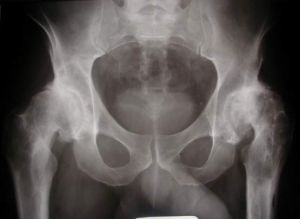

二、髓痛

關節痛1.股骨頸骨折此病相當常見,50-70歲者最多佩。可分不完全骨折和無移位骨折及移位骨折前者骨折後僅感髓部疼痛,尚能站立行走或騎腳踏車,後者則有屈髓屈膝及外鏇畸形以及骨摩擦感髓關節後上脫位傷肢呈典型屈曲,內收及內鏇畸形丶,不能外鏇二者應鑑別診斷。外傷史及X線平片可確診。

2.股骨頭骨髓滑脫外傷可導致骨髓移位,自發性骨髓滑脫可繼發於敗血症、腎性佝僂病軟骨發育不全及多發性骨髓發育異常等。

自發性股骨頭骨髓自然滑脫較為少見髖部疼痛關節活動障礙X線拍片即可確診本病。

3.類風濕性俄關節炎本症為一種全身性疾病,可發生任何年齡。早期關節有晨僵現象隨後逐漸髓痛。實驗室檢查及X線檢查協助診斷。

4.強直性脊柱炎本症是脊柱的慢性進行性炎症,侵及骰骼關節,關節突及附近韌帶和軀幹的大關節導致纖維性骨性強直和畸形,下腰背疼痛和強硬;胸廓疼痛和僵硬,腰椎活動受限;擴胸受限虹膜炎病史可作為診斷標準。HLA-B27X線拍片人T可協助診斷。

5.化膿性髓關節炎本症為一種急性的嚴重關節感染。多發於少年兒童,由於髓關節的部位深在周圍肌肉厚,容易延誤診斷,影響治療導致關節強直,喪失功能,造成殘廢。

6.髖關節結核一般發病隱漸,早期症狀為髓部疼痛,逐漸加重可有結核病中毒症狀。X線檢查對本病的早期診斷極為重要。

7.暫時性骨膜炎本症為一種可自愈的非特異性炎症。其特點為疼痛症狀在數周內消失並持久康復。實驗室檢查無明顯異常x線表現有髓關節囊腫脹陰影、臀小肌平直陰影變為弧影、關節間隙增寬

8.股骨頭缺血性壞死由於骨缺血而導致的骨壞死病,已成為現代醫學發展中常見的疾患之一。多種病因可造成股骨頭缺血性壞死其共同症狀即有髓部疼痛,呈隱漸性鈍痛,可出現破行等臨床症狀X線拍片,CT、MRI是診斷本病的常用方法

9.夠關節骨性關節病本病可分原發性與繼發性兩種,病理變化從軟骨變化,軟骨下骨質病變為主臨床症狀的特點是起病緩慢,酸脹痛的輕重與X線的表現不成正比。嚴重患者可出現關節僵硬破行。本病疼痛開始由坐站立時疼痛最為明顯丶,經過活動以後關節又見靈活,酸脹痛也漸減輕。但過度活動又會引起酸脹痛和運動受限

10.航部軟組織疾患如坐骨神經盆腔出口狹窄症,梨狀肌綜合徵,編部滑囊炎臀肌攣縮症等均可起髓關節部位的疼痛,應當細心鑑別。

11.髓部腫瘤及瘤樣病變多見的有骨軟骨瘤、軟骨瘤、骨巨細胞瘤骨囊腫、動脈瘤樣骨囊腫、骨纖維結構不良滑膜軟骨瘤病、骨肉瘤。軟骨肉瘤骨纖維肉瘤、滑膜肉瘤、轉移瘤等這些病變不同程度的導致髓部疼痛X線檢查協助診斷,活組織檢查可以確定診斷。

12.著色性絨毛結節性滑膜炎,血友病性關節炎,剝脫性骨軟骨炎等病症也經常發生在髓關節同樣引起碗的疼痛。